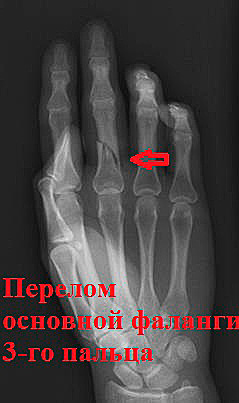

Пациент С. 23 года. травма при ударе кулаком о боксерскую грушу. Диагностирован типичный для этого вида травмы перелом 5 плюсневой кости.

В связи с неудовлетворительным положением отломков после репозиции было принято решение выполнить операцию.

Положение на отломков на контроле удовлетворительное.